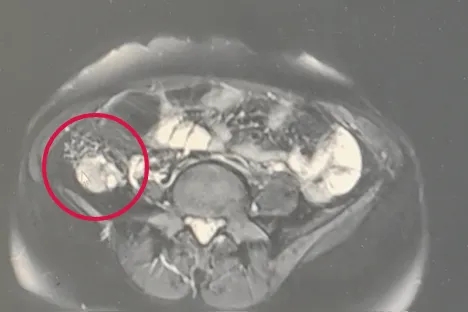

卵巢癌,这位潜伏在女性生殖系统的"沉默杀手",其发病率在妇科恶性肿瘤中位列第三,仅次于宫颈癌和子宫内膜癌。然而令人警醒的是,卵巢上皮癌的致死率却高居妇科肿瘤之首,犹如一柄悬在女性健康之上的达摩克利斯之剑。由于卵巢复杂的胚胎发育历程、精微的组织结构以及多变的内分泌功能,使得早期症状如同雾里看花,难以捉摸。更棘手的是,术前准确判断肿瘤性质犹如在迷宫中寻找出路,充满挑战。其中上皮癌最为常见,像贪婪的侵略者般占据主导,而恶性生殖细胞肿瘤则紧随其后。令人扼腕的是,确诊时仅有30%的患者肿瘤还"安分"地停留在卵巢,大多数已经像溃堤的洪水,蔓延至子宫、输卵管、大网膜等盆腔器官,这也让早期诊断成为医学界亟待攻克的难题。